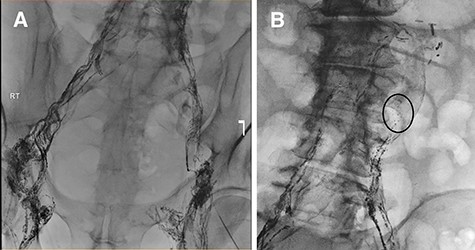

Failure of conservative management leads to an unsuccessful attempt at lymphatic embolization (Fig. 2a and b). Therefore, the morning of surgery, olive oil was administered orally and lymphatic leakage was identified intraoperatively and sealed using glue. The abdomen was closed with no obvious ongoing lymphatic leak. Full diet was implemented and tolerated with no further ascites.

(A) Lymphangiogram and unsuccessful attempt at cannulating pelvic lymphatic channels. (B) Lymphatic leak is seen at the left of the L3-L4 level.